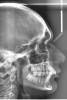

geelros Опубликовано 26 июля, 2012 Поделиться Опубликовано 26 июля, 2012 (изменено) Всем привет.Год назад планировал ставить БС, посетил 3-х врачей, включая Force (Алексей Ермаков).Потом БС отошли на второй план, вернулся к принятию решения только сейчас, посетил ещё одного ортодонта.В итоге мнения лечения почти у всех разнились.Первый врач предлагал удалять 4ки.Второй врач(в институте стоматологии на долгоруковской) - взрослая женщина. Предлагала ставить БС без удаления, про удаление думать в процессе лечение, но по примерным расчетам удаление не нужно.Третий врач - Алексей. Решил поехать к нему после чтения форума и его ответов разным пользователям, понравились мнения и тд. Ездил к нему в зеленоград, консультация понравилась, подход понравился. Объяснил, что удалять 4ки глупость, ухудшится профиль. Предложил удалять восьмерки. Удаление это единственное, что меня загрузило на тот момент, очень этого не хотелось. Считал его мнение самым объективным.В итоге этого всего потерял год Неделю назад, стечением обстоятельств, попал ещё к одному ортодонту ( девушке), по возрасту примерно как и Алексей. Сделала слепки(самые простые, для конкретного лечения, помойму, делаются другие), взяла снимки, посчитала - сказала, что нужно делать без удаления (считает, что любое удаление может привести к ухудшению профиля), и необходимо расширять нижнюю челюсть (если не ошибаюсь в формулировке лечения, т.к. столько уже версий слышал ) Естественно хочется без удаления, одна восьмерка торчит (неправильно, под углом), второй ещё нет. Читал и видел на примерах, как это бывает болезненно, да и не хочется удалять здоровый зуб. Также читал мнения, что удаление это самый простой способ, есть место для маневрирования и поэтому ортодонты часто предлагают такой способ лечения. К кому попаду в итоге, не знаю, до этого все время хотел к Форсу. У последнего ортодонта есть возможность сделать дешевле..Хотелось бы услышать советов, рекомендаций, объективного мнения.Буду рад любому диалогу. Призываю в пост Форса ТРГ и панораму прилагаю. P.S 23 года. Изменено 26 июля, 2012 пользователем geelros Ссылка на комментарий